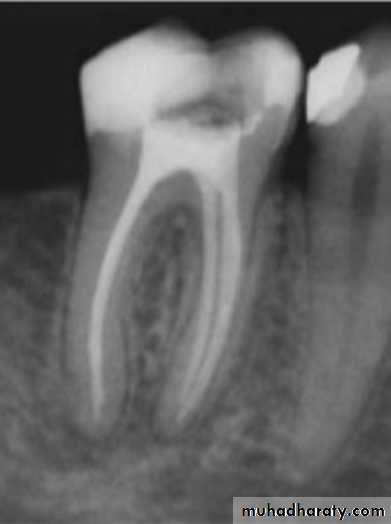

• Do not adhere to dentin.

Gap location between gutta percha and the root dentin